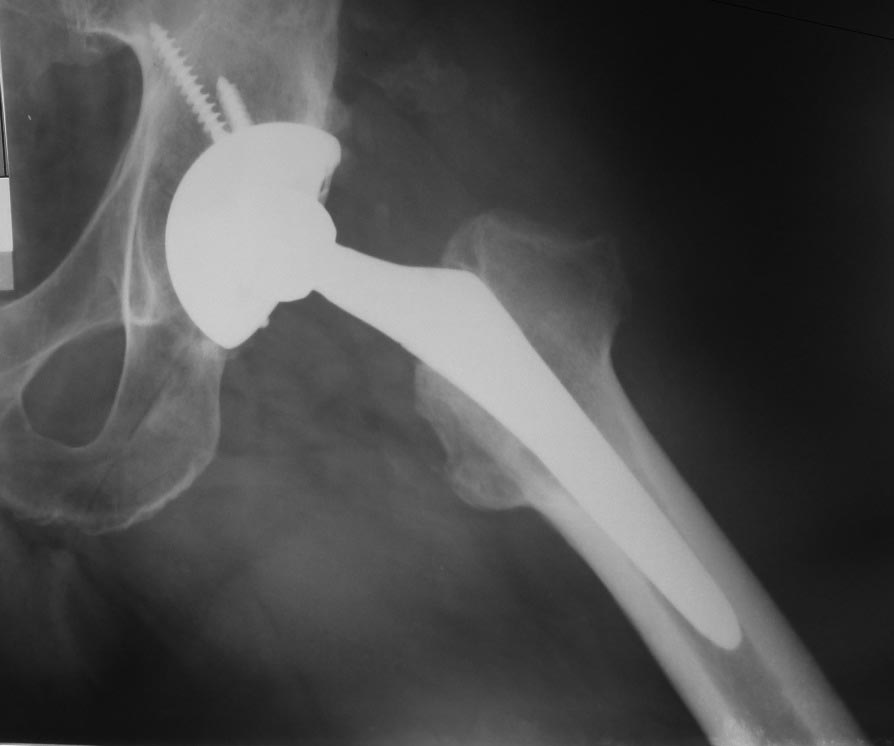

Эндопротезирование пациенту 49 лет выполнил в 2007 г. по поводу

коксартроза. В начале мая 2013 г. в состоянии запоя он упал со скамейки,

Последние (июньские) рентгенограммы без особенностей (прилагаются).